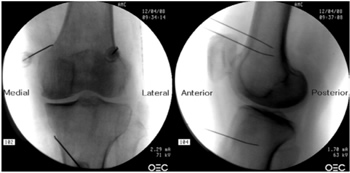

Radiofrecuencia de los nervios geniculados guiados por fluoroscopia

Para realizar una RFTNG guiados por fluoroscopia necesitamos una visión anteroposterior (AP) y lateral de la rodilla (Figura 2). Primero ubicamos al paciente en posición supina con una almohada debajo de la fosa poplítea (para que esté más cómodo) (16). Después de realizar asepsia y antisepsia de la rodilla, procedemos a ubicar los NG (Tabla II). El NGSL se encuentra avanzando la aguja de RFT hacia la confluencia de la diáfisis femoral lateral con el cóndilo femoral lateral en una visión AP y en un punto medio del fémur en una visión lateral. El NGSM se localiza avanzando la aguja hacia la confluencia de la diáfisis femoral medial con el cóndilo femoral medial en una visión AP y en un punto medio del fémur en una visión lateral. Por último, el NGIM se localiza avanzando la aguja hacia la confluencia de la diáfisis tibial medial con el epicóndilo tibial en una visión AP y en un punto medio de la tibia en una visión lateral (16,17).

Fig. 2. Proyección AP y lateral donde se observan las dianas terapéuticas usando fluoroscopia. Imagen tomada del artículo de Choi y cols. (9). Reproducido con la autorización de Jin Woo Shin.

Tabla II. Localización de los nervios geniculados guiados por fluoroscopia

Es muy importante tener una buena visión AP y lateral. En la proyección AP, la articulación tibiofemoral debe tener una anchura similar a ambos lados de la rodilla con el interespacio abierto (9). En la proyección lateral, debe existir una correcta superposición de ambos cóndilos femorales para realizar un bloqueo satisfactorio de los NGSM y NGSL (18).

La mayoría de autores toman las referencias descritas previamente para localizar estos nervios por fluoroscopia, excepto Fonkoué y cols. (18), quienes encuentran que las dianas terapéuticas del NGSM y NGSL (en una visión lateral) se encuentran en la unión del borde superior de sus respectivos cóndilos femorales con la corteza posterior de la diáfisis del fémur, y no en la mitad del espesor del fémur, como se describe clásicamente (9,10,13).